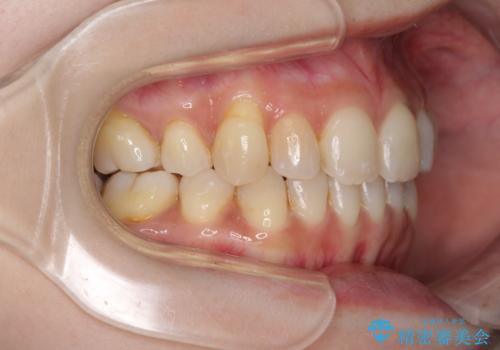

- 上下前歯の叢生を気にして来院された患者様です。

費用を抑え、期間もあまりかけずに治療をしたいとのことで、インビザライン・ライトを用いて矯正治療を行うこととしました。

インビザライン・ライトは、製作できるアライナーの枚数に制限があるため、移動可能な量に限りがあります。

一方で、半年程度で治療を終えることができるため、軽度の歯列不正の患者様には大変お勧めです。